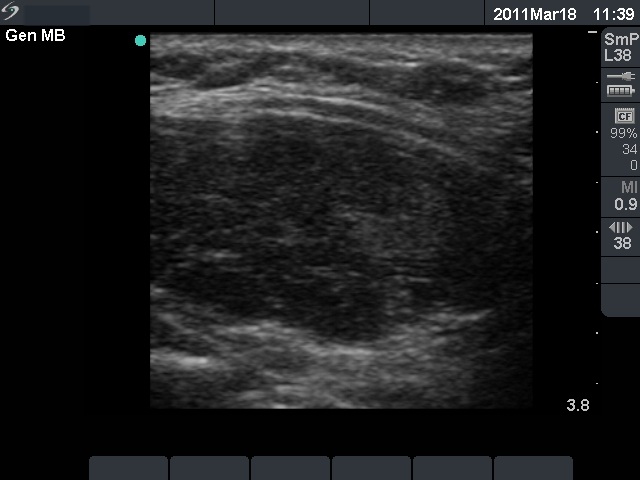

Ultrasonography: revealed hypoechogenic inhomogeneous thyroids with an echonormal circumscribed lesion in the left lobe corresponding to a secondary lobule.

Combined ultrasonographic-cytological diagnosis: benign Hashimoto's thyroiditis.

Follow-up investigations: one year later subclinical hypothyroidism developed. The sonographic picture had also changed: the discrete lesion in the left lobe disappeared.